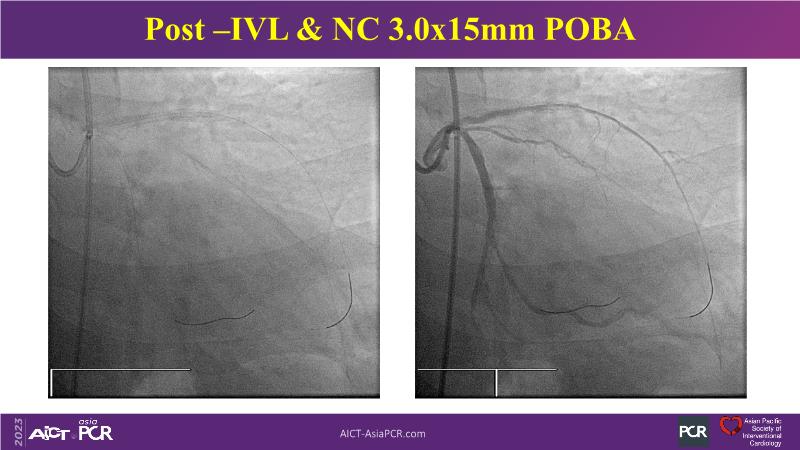

Revolutionising coronary calcium treatment: unleashing the potential of intravascular lithotripsy

Over the last five years, we have learned that there is a new tool for treating calcium, the greatest enemy of interventional cardiology, which can take various forms: intravascular lithotripsy. In this session, look at how to master this technique in different scenarios, from eccentric calcified lesions to left main bifurcations.

- To uncover practical tips and techniques for IVL in challenging calcified lesions: eccentric calcified lesions